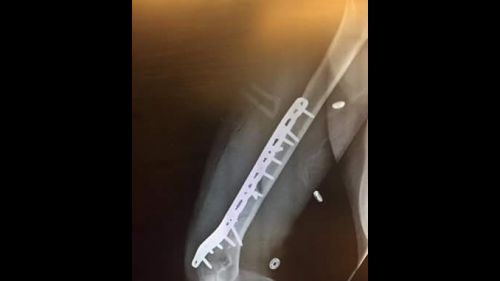

Lindsey Vonn si frattura l'omero in allenamento. Le sue prime parole